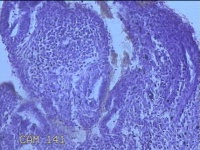

宫腔内容物

性别

女

年龄

36岁

临床诊断

不完全性自然流产并发盆腔感染

一般病史

停经3月余,阴道流血1月余。

标本名称

大体所见

灰白暗红色不规则碎组织2x1.8x0.3cm一堆,未发现明显的绒毛样组织。